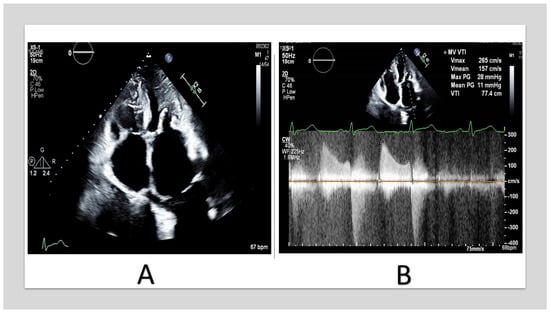

Figure 3.

TTE of 57_year_old woman with end-stage renal disease. (A) shows severe MAC involving the anterior and the posterior annulus with extension to the leaflets and the chordae. (B) shows mitral inflow continuous-wave Doppler with mean gradient of 11 mmHg. (TTE: transthoracic echocardiography, MAC: mitral annular calcification).